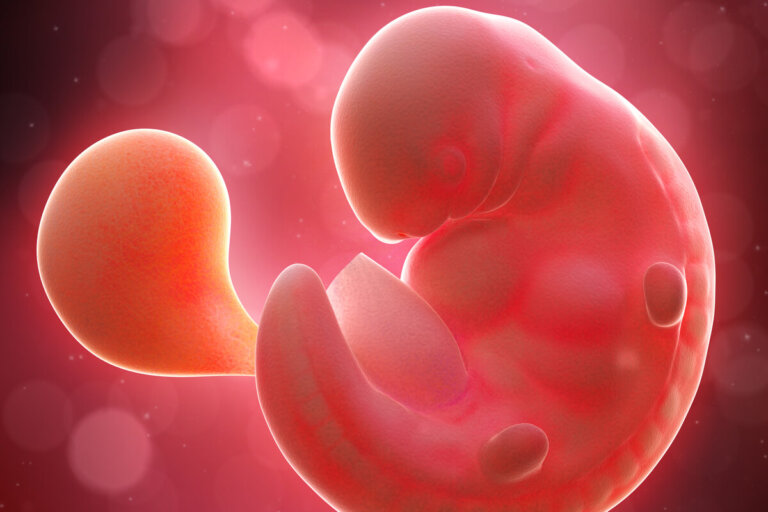

Este será el aspecto que tendrá tu bebé en una ecografía durante las semanas 6 y 7 del embarazo: